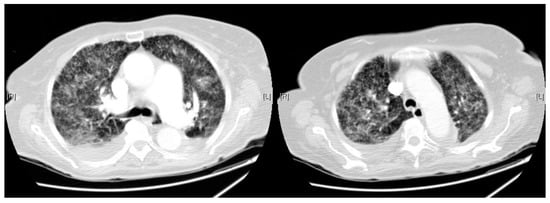

Chest CT scan revealed an extensive pulmonary parenchymal involvement consisting of irregular septal thickenings with ground-glass areas and centrilobular nodules with a peri-lymphatic distribution, which had a predominantly central distribution although it affected the entire parenchyma of both hemithorax without apico-basal gradient (Figure 3).

Figure 3.

Chest CT on 10th day: Extensive pulmonary parenchymal involvement consisting of irregular septal thickenings with ground-glass areas and centrilobular nodules with a peri-lymphatic distribution.